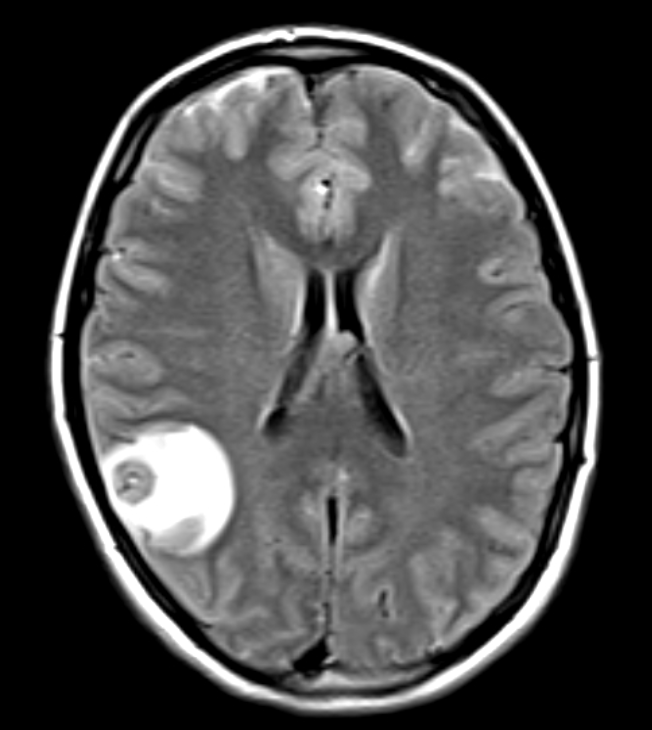

Adult onset seizure in an immigrant from Argentina (5 years ago). No PMH. PE normal. CBC and CMP WNL. MRI shown below:

Neuroimagin reveals a scolex

Neurocystercosis: pork tapeworm (Taenia solium) which is endemic to developing countries. Presents with adult onset seizure and evidence of at least one or more cystsin the brain parenchyma. Tx with corticosteroids and albendazole.

Can look like this

What are the imaging findings:

Scolex: part of tanea solium worm that attaches with 4 suckers along with an engancing lesion with vasogenic edema (consistent with degenerating cyst).